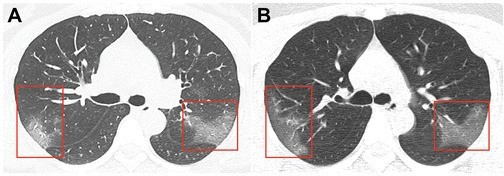

Jurnalda dərc edilmiş təsvirlər Çinin Lançjou şəhərində 39 dərəcə temperaturla xəstəxanaya yerləşdirilmiş 33 yaşlı qadının kompüter tomoqrafiyası nəticəsində alınıb.

Birinci şəkildə "tutqun şüşə effekti”ni yaradan bulanıqlıq görünür. Üç gün sonra çəkilmiş ikinci şəkildə isə virusun genişlənmiş sahəsini görmək mümkündür.